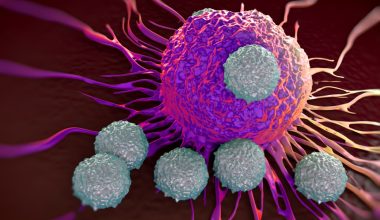

Το φάρμακο, που αναπτύχθηκε από τη φαρμακευτική εταιρεία Kintor, μπλοκάρει τις επιπτώσεις των ορμονών ανδρογόνων, απενεργοποιώντας τους σχετικούς υποδοχείς στην επιφάνεια των κυττάρων. Η πρωτεΐνη-ακίδα του κορωνοϊού, προτού διεισδύσει στα ανθρώπινα κύτταρα και τα μολύνει, πρέπει να ενισχυθεί από μια πρωτεΐνη (TMPRSS2) που ρυθμίζεται από τους κυτταρικούς υποδοχείς ανδρογόνων. Το συγκεκριμένο μη στεροειδές φάρμακο εμποδίζει αυτή τη διαδικασία, δυσκολεύοντας έτσι στη συνέχεια τη μόλυνση των κυττάρων από τον ιό SARS-CoV-2.